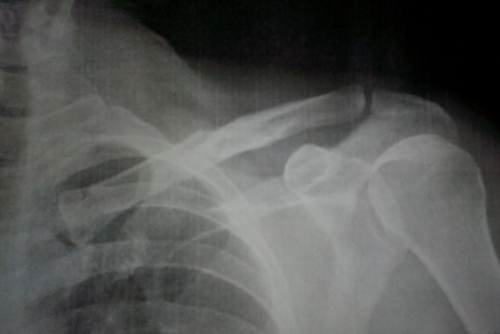

Is it really over 2 month since I wrote the Albir Lighthouse article, it doesn't seem that long. February started with so much promise, unfortunately circumstances took over a little and plans went out the window, when I managed to break my collarbone in a mountain biking accident...